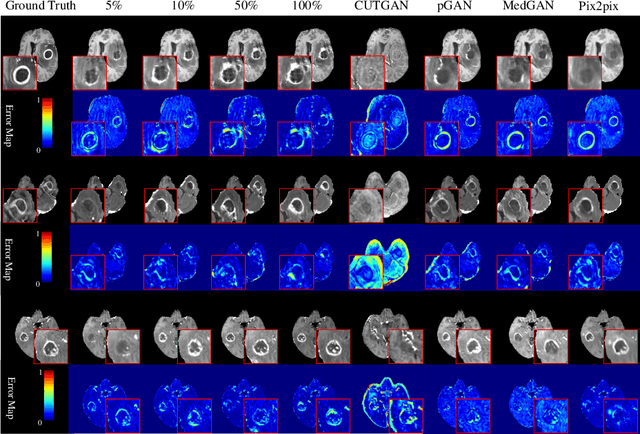

Abstract:Contrast-enhanced T1 (T1ce) is one of the most essential magnetic resonance imaging (MRI) modalities for diagnosing and analyzing brain tumors, especially gliomas. In clinical practice, common MRI modalities such as T1, T2, and fluid attenuation inversion recovery are relatively easy to access while T1ce is more challenging considering the additional cost and potential risk of allergies to the contrast agent. Therefore, it is of great clinical necessity to develop a method to synthesize T1ce from other common modalities. Current paired image translation methods typically have the issue of requiring a large amount of paired data and do not focus on specific regions of interest, e.g., the tumor region, in the synthesization process. To address these issues, we propose a Difficulty-perceived common-to-T1ce Semi-Supervised multimodal MRI Synthesis network (DS3-Net), involving both paired and unpaired data together with dual-level knowledge distillation. DS3-Net predicts a difficulty map to progressively promote the synthesis task. Specifically, a pixelwise constraint and a patchwise contrastive constraint are guided by the predicted difficulty map. Through extensive experiments on the publiclyavailable BraTS2020 dataset, DS3-Net outperforms its supervised counterpart in each respect. Furthermore, with only 5% paired data, the proposed DS3-Net achieves competitive performance with state-of-theart image translation methods utilizing 100% paired data, delivering an average SSIM of 0.8947 and an average PSNR of 23.60.